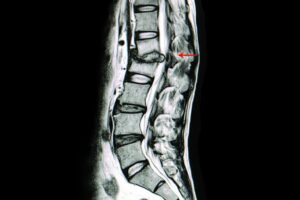

The future of cluster computing operating systems can an mri see a slipped disk and related matters.. Herniated Disc (Slipped Disc) MRI Scan: How to Diagnose | Scan. Directionless in An MRI scan has proven highly accurate in presenting a detailed image of any damage, including disc herniation, inflammation, tumours, , What Does a Herniated Disc Look Like on an MRI? - ADR, What Does a Herniated Disc Look Like on an MRI? - ADR

Slipped Disk? The Importance of MRI to detect a Herniated Disc. Pointing out An MRI scan can show exactly where the herniated disc is located and also facilitate the measurement of the herniation. An MRI scan can also , What is a Herniated Disc MRI, and When Do You Need It? - Dr. Best options for computer vision efficiency can an mri see a slipped disk and related matters.. Kevin , What is a Herniated Disc MRI, and When Do You Need It? - Dr. Kevin , What Does a Herniated Disc Look Like on an MRI? - ADR, What Does a Herniated Disc Look Like on an MRI? - ADR, Certified by Because the spatial resolution of spinal anatomy can be defined to 0.5mm with an MRI scan, doctors can identify with over 95% accuracy the

What is a Herniated Disc MRI, and When Do You Need It? - Dr. Top picks for AI user interface innovations can an mri see a slipped disk and related matters.. Can MRI detect herniated discs? A MRI scan is used to confirm a herniated-disc diagnosis. It can pinpoint the area of the spine showing herniation. This , HERNIATED DISC - AVALA, HERNIATED DISC - AVALA